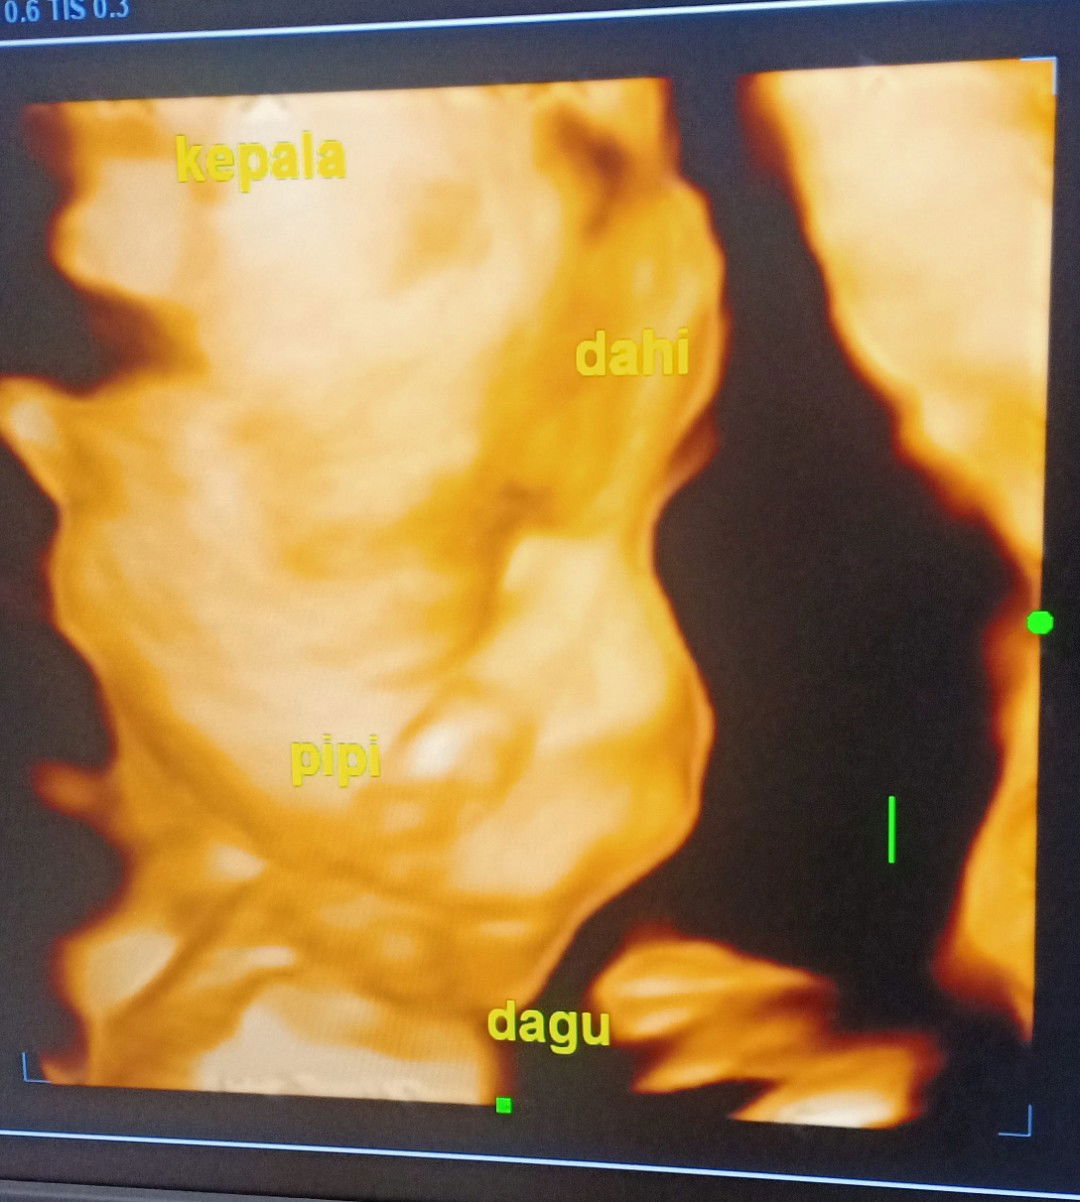

34weeks yg nano nano nikmatnya

Sharing yuk bun yg udah trismester 3 udah ngerasain apa aja... Saya udah 34weeks ... nyeri2 sedap di bagian miss v , tulang punggung berasa mau patah,, Tidur udah engap bgt ,, susah tidur gak enak semua🤭🤭 Tapi menikmati sekali semester akhir yg nano-nano ini... Bunda udah ngerasain apa aja???? #bantusharing #justsharing #34weeks